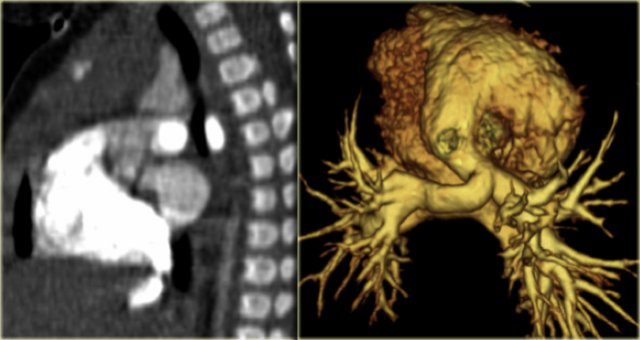

On the left a 2 month old boy with heart failure.

First study the image, then continue

The findings are:

• Large thymus which is normal for a 2 month old.

• Striking discrepancy between diameter of ascending and descending aorta.

The diagnosis is coarctation, which is nicely demonstrated on the posterior view of the reconstruction.

There are two types of coarctation.

The type we usually see is the post-ductal type, which is distal to the left subclavian artery.

The uncommon pre-ductal type is seen in neonates.

They present with severe heart failure, mostly within the first week of life, usually on the first day.

The occlusion is in front of the left subclavian.